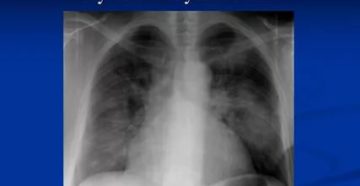

Пневмонит (пульмонит, альвеолит) Пневмонитом называется воспаление альвеолярных стенок и интерстициальной ткани легких. Со временем в…

Саркоидоз легких Саркоидоз представляет собой доброкачественный процесс гранулематоза тканей, затрагивающий преимущественно легкие. Он легко поддается…